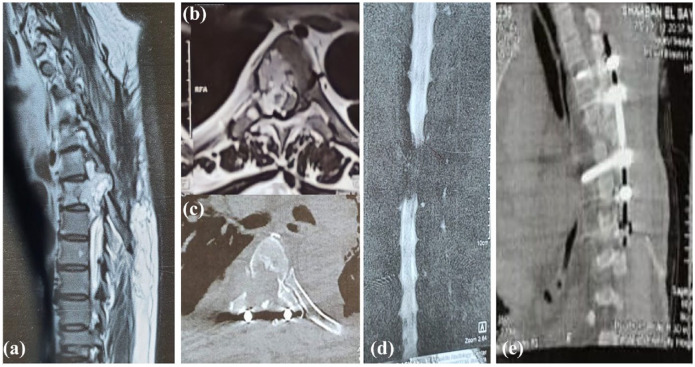

脊索瘤是一种生长缓慢、局部浸润性的低级别肿瘤,属于肉瘤家族。它主要侵犯骶骨和颅底。我们报告了一例最初表现为硬膜外血肿(EDH)的胸脊索瘤病例,这是一种罕见的临床实体瘤。我们在报告该病例的同时,还对文献中的类似病例进行了PRISMA驱动的系统综述。该综述包括胸椎脊索瘤的临床特征和预后。我们的病例涉及一名 60 岁的男性,尽管他没有外伤史,但却出现了急性截瘫。在 T6 水平发现硬膜外血肿,因此进行了 T4-6 椎板切除和固定手术。手术后六个月,患者下肢逐渐出现无力和痉挛。计算机断层扫描(CT)显示,T6受到侵蚀,并伴有侵袭性肿块。磁共振成像(MRI)显示,D6的椎体和右侧椎弓根处有一个巨大的异质软组织肿块,突出于硬膜外腔,并在该水平压迫脊髓。肿块大小约为 5 × 4 × 3.5 厘米。磁共振脊髓造影显示,T5-6水平有充盈缺损,证实软组织病变位于椎管内。完全切除肿块后,确诊为胸脊索瘤。术后随访显示,患者的下肢痉挛和截瘫症状明显改善,并开始接受辅助放疗。本病例强调了在评估类似 EDH 的表现时保持高度怀疑的重要性。

A chordoma is a slow growing, locally invasive, low-grade tumor belonging to the sarcoma family. It mainly affects the sacrum and skull base. We present a case of thoracic chordoma initially presented with epidural hematoma (EDH), which is a rare clinical entity. We reported this case, and also performed a PRISMA-driven systematic review to summary the similar cases in the literature. This review includes the clinical characteristics and outcome of thoracic chordoma. Our case involves a 60-year-old male who, despite no history of trauma, presented with acute paraparesis. An epidural hematoma was identified at T6 level, leading to a surgical intervention involving T4-6 laminectomy and fixation. Six months subsequent to surgery, the patient experienced progressive lower limb weakness and spasticity. Computed tomography (CT) exhibited erosion of T6 and an associated aggressive mass. Magnetic resonance imaging (MRI) revealed a large heterogenous soft tissue mass arising from the vertebral body and right pedicle of D6, protruding in the epidural space and compressing the spinal cord focally at this level. The mass measured approximately 5 × 4 × 3.5 cm. Magnetic resonance myelography indicated a filling defect at T5-6 level, confirming the intraspinal location of the soft tissue lesion. Complete excision of the mass confirmed the diagnosis of thoracic chordoma. Postoperative follow-up demonstrated notable improvement in the lower limb spasticity and paraparesis, and the patient started adjuvant radiotherapy. This case underscores the importance of maintaining a high index of suspicion when evaluating presentations resembling EDH.